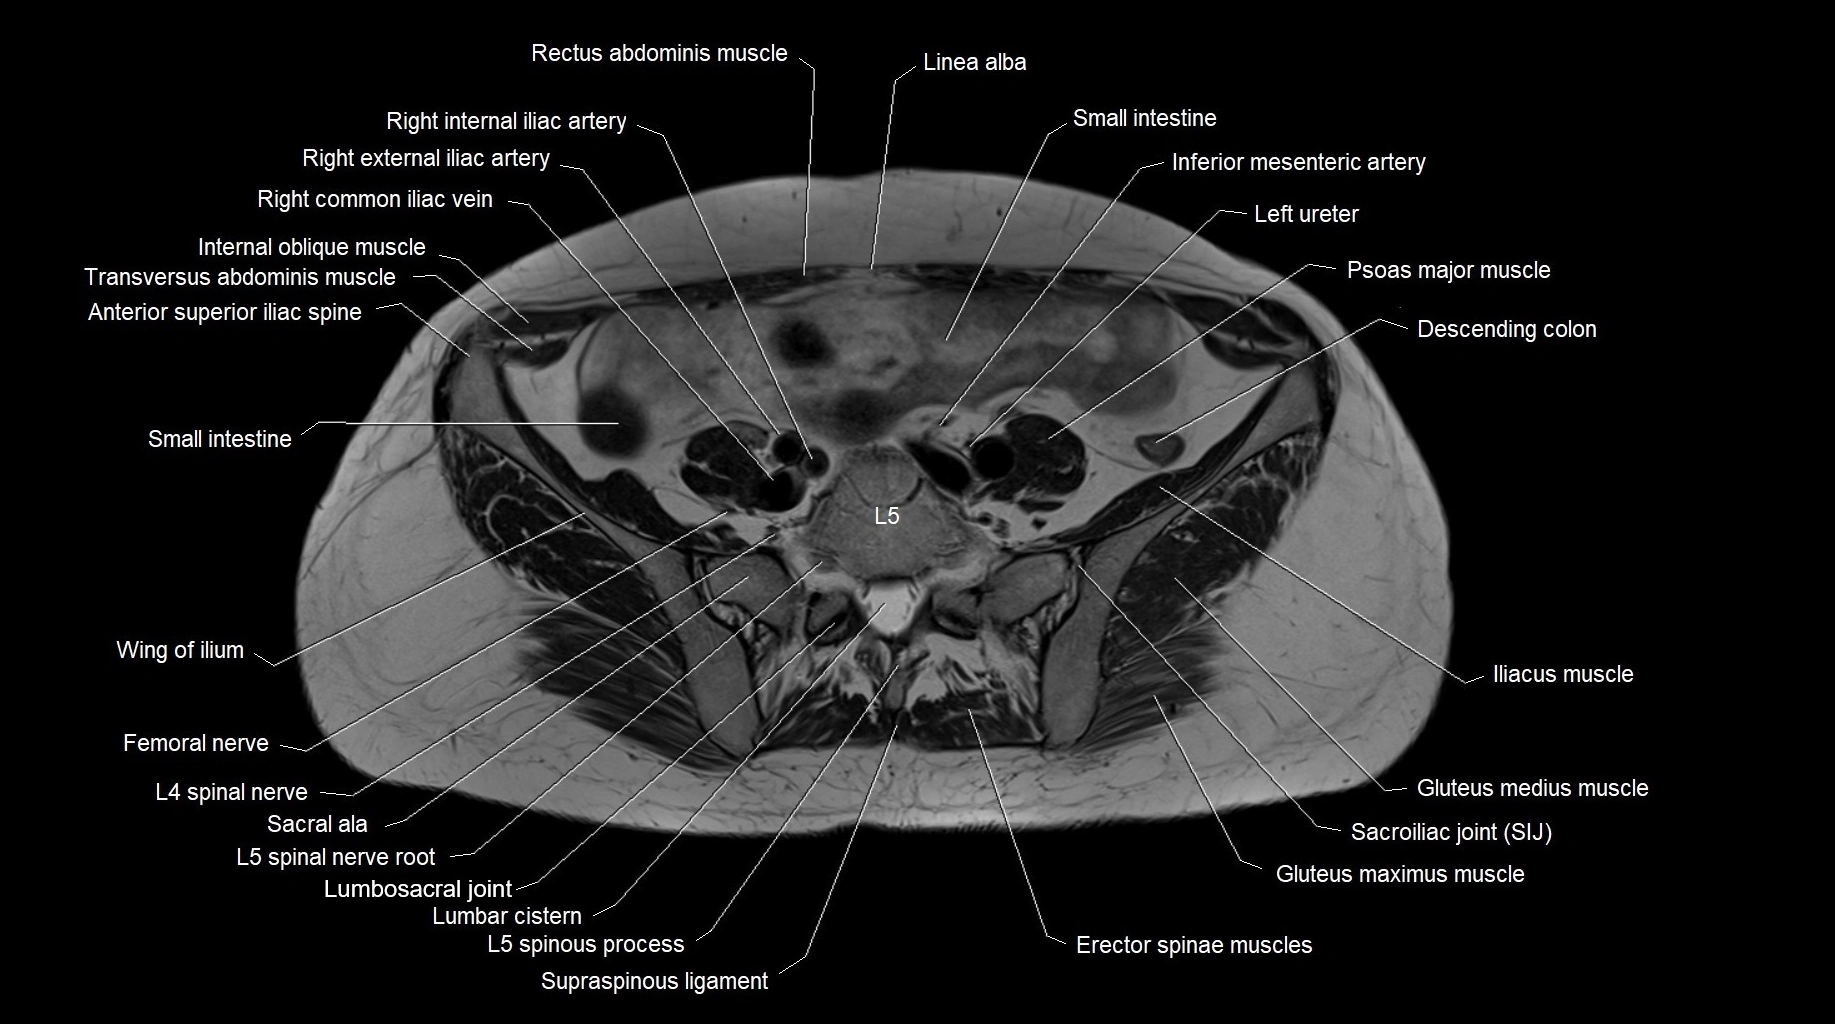

MRI images